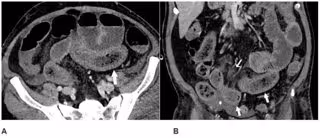

Se observaron anormalidades intestinales en el 31 por ciento de las tomografías computarizadas (3,2% de todos los pacientes) y fueron más frecuentes en pacientes ingresados en una Unidad de Cuidados Intensivos (UCI) que en otros pacientes hospitalizados. Los hallazgos intestinales incluyeron engrosamiento y hallazgos de isquemia tales como neumatosis (gas en la pared intestinal).

"Encontramos anormalidades intestinales en las imágenes en pacientes con Covid-19, especialmente en pacientes más graves ingresados en una UCI", han explicado los investigadores, quienes han informado de que la isquemia intestinal en algunos pacientes puede estar causada por coágulos sanguíneos pequeños.

"Los pacientes en la UCI pueden tener isquemia intestinal por otros motivos, pero sabemos que el Covid-19 puede provocar coagulación y lesiones en los vasos pequeños, por lo que el intestino también podría verse afectado por este virus", han apostillado los científico.